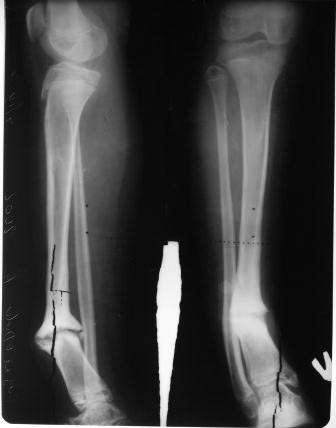

Коллеги, обратилась пациентка 12 лет, со слов матери 5 лет

назад  заболела острым гематогенным остеомиелитом, 4 раза оперирована в

обл. детской больнице, после образовался ложный сустав,  в центре

произведена  костная аутопластика, нагноение, после отторжения аутокости

рана зажила и рецидив псевдоартроза 2 года назад(все это со слов

матери). Клинически тугой ложный сустав н/з голени,

деформация,укорочение 2см, девочка ходит самостоятельно,прихрамывает.

Прилагается  Р-граммы, обещают принести и предыдущих